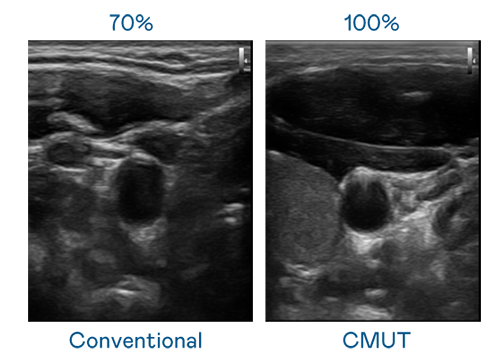

CMUT 技术是一种用电容式微机电元件来产生超音波讯号的技术。与传统 PZT 压电式技术相比,CMUT 频宽增加 30%,更宽频的超音波讯号让影像解析度大幅提升,是实现高影像品质医疗超音波扫描、促进精准医疗发展的关键技术。

大频宽带来超清晰影像

超音波影像的解析度高低,首先取决于探头能发出的讯号频宽。朋友换娶4完整版中文翻译 CMUT 可提供高清晰的超音波讯号,提供高频宽、高灵敏度、影像纹理细节更高的超音波影像,协助医护人员缩短影像判读时间及利用精准的医疗影像进行诊断。